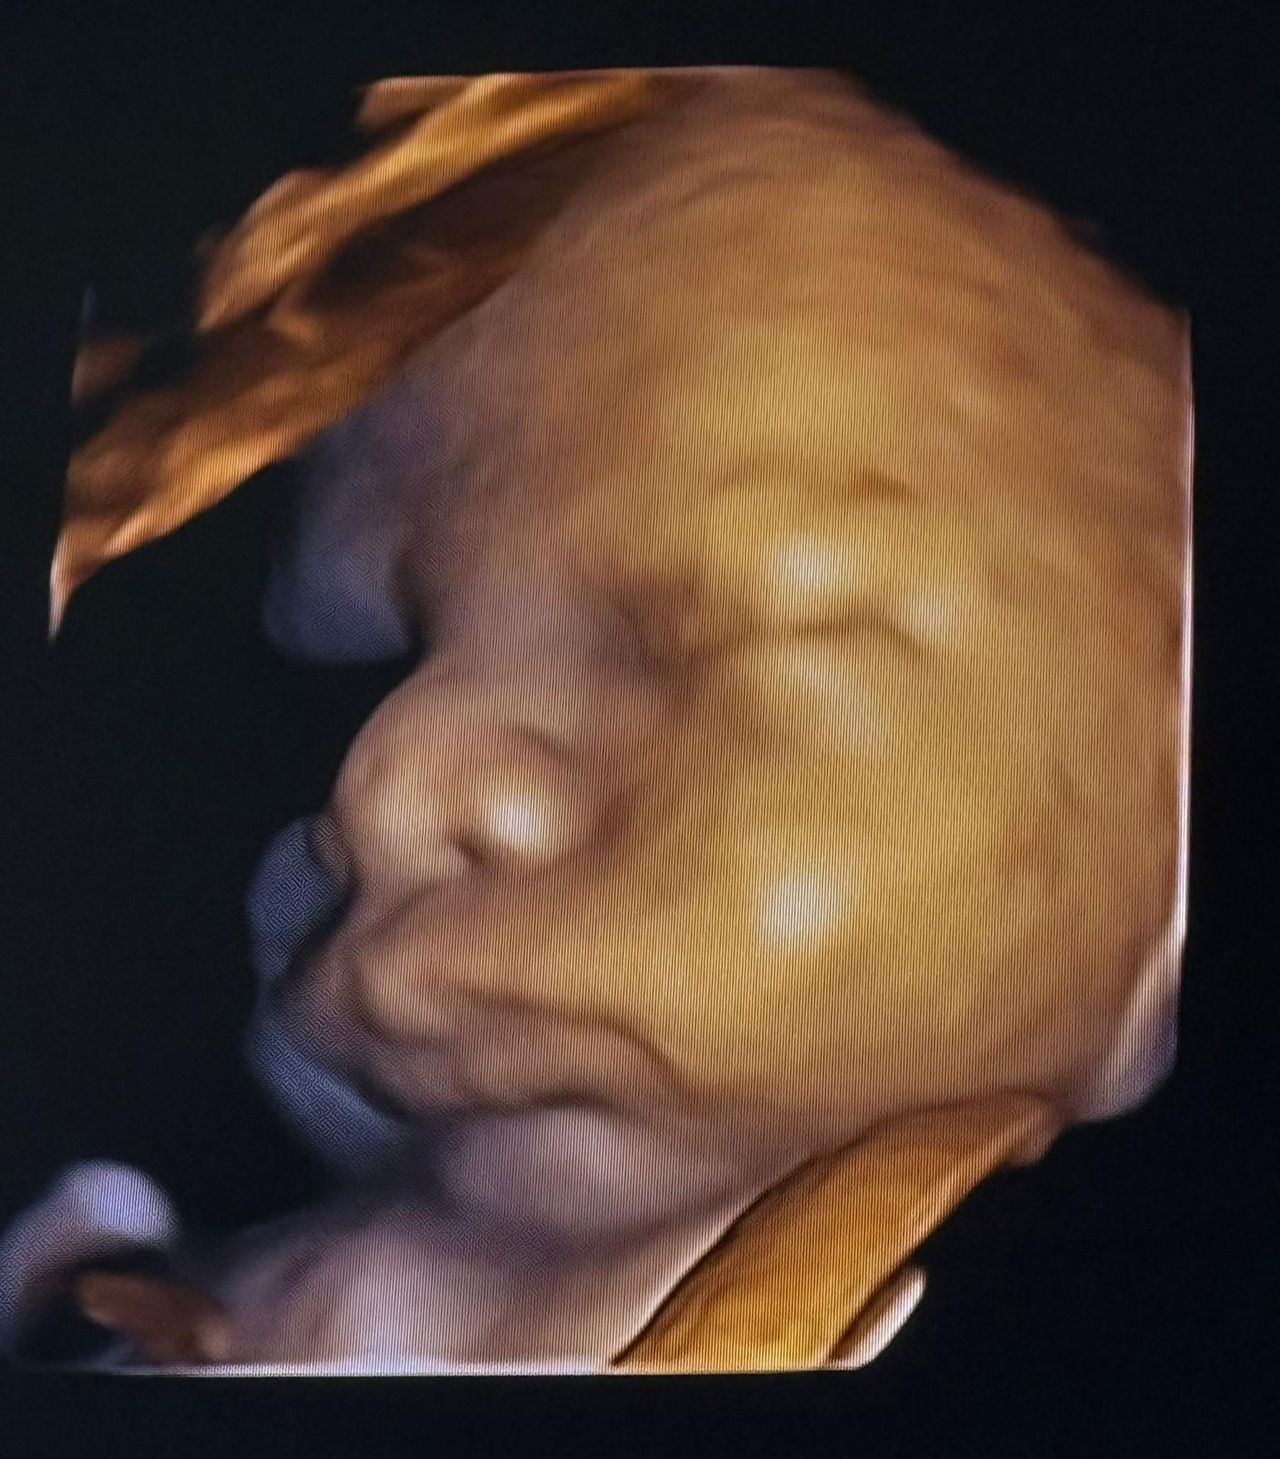

• Ecografie ginecologiche e ostetriche in tutti i trimestri di gravidanza

• Ecografie 3D e valutazioni specifiche tra l’XI e la XIV settimana

• Ecocardiografia fetale per lo studio approfondito del cuore del bambino

• Ecografia 3D ginecologica e ostetrica